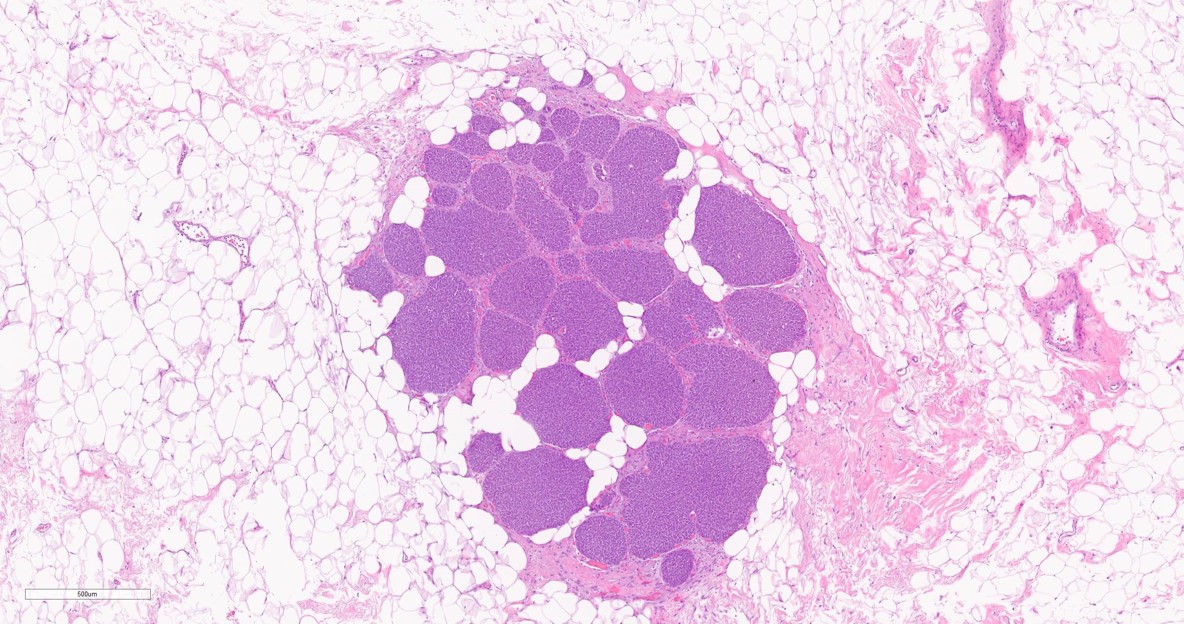

Breast lesion diagnosis ? See poll below 👇

#breastpath #pathresidents #pathtwitter #BreastPatholog1